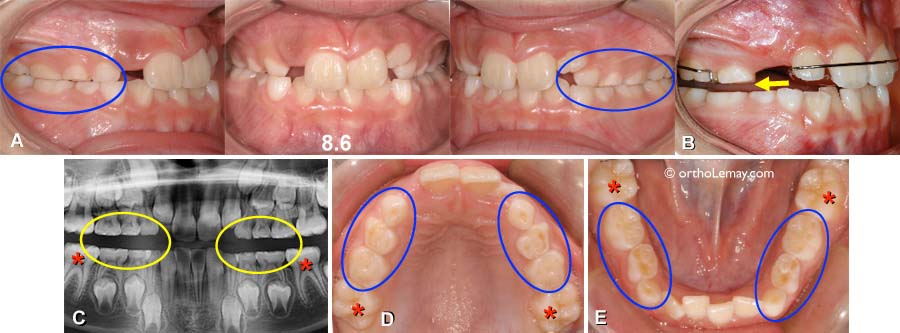

Tâche jaune dent bébé Bébé tâches jaunes sur les dents Publié dans Questions en tout genre amanga59 le 5 mars 11 à 17 h 14 min # Bonjour à toutes, J'ai une question mon bébé a 15 mois et a des petit L'hypominéralisation des molaires et des incisives (MIH) Se présentant sous la forme d'une coloration allant du blanc crémeux au jaune brun et touchant principalement lesINSCRIVEZVOUS A NOTRE NEWSLETTER Restez motivé pour brosser, recevez les dernières infos et ne ratez aucune offre En vous inscrivant, vous confirmez le fait que vous avez lu et accepté la politique de confidentialitéLes dents chez un enfant, comme chez les adultes, peuvent avoir différentes nuances grisâtres, bleuâtres, jaunâtres Mais parfois les parents remarquent que l'enfant a des dents jaunes Cette couleur de dents peut être chez les enfants d'âges différents Dans certains cas, l'enfant peut déjà couper une dent jaune

L Hypomineralisation Molaire Incisive Mih Qu Est Ce Que C Est

La Mih Une Maladie Des Dents De L Enfant Encore Meconnue